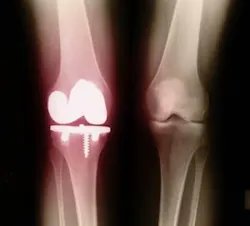

Glucosamine and chondroitin are somewhat helpful to treat pain and the loss of function associated with osteoarthritis in joints. Glucosamine usually is derived from the shells of shellfish. Chondroitin comes from cartilage, usually from shark and cow cartilage. Combined, they have been shown to rebuild human cartilage around joints, although the FDA has not allowed such a health claim. Some studies show chondroitin offers about an 8-10-percent joint mobility improvement, although it works slowly (three months or more).